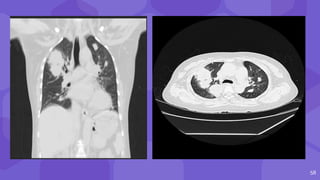

⬢ diffuse parenchymal complications- CT demonstrates

decreased graft enhancement, with no contrast excretion in

excretory phase,

⬢ loss of corticomedullary differentiation on T1-weighted

images is nonspecific

⬢ but indicative of the presence of diffuse parenchymal

complications and impaired graft function

54 ⬢ diffuse parenchymalcomplications- CT demonstrates decreased graft enhancement, with no contrast excretion in excretory phase, ⬢ loss of corticomedullary differentiation on T1-weighted images is nonspecific ⬢ but indicative of the presence of diffuse parenchymal complications and impaired graft function

• #55 In these diffuse parenchymal complications, CT demonstrates decreased graft enhancement, with no contrast excretion in excretory phase Loss of corticomedullary differentiation on T1-weighted images on MRI finding in acute rejection.

• #59 Hrct shows soft tissue density in right upper lobe with central cavity and air lucencies and surrounding ggo